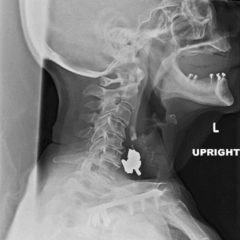

The frontal view of the right foot showed divergent dislocation of the second through fifth metatarsal bones (red outlines) consistent with Lisfranc injury. Though the Lisfranc ligament is not visualized by radiograph, the yellow markings represent the location of the Lisfranc ligament between the medial cuneiform (blue dot) and the base of the second metatarsal bone. The first metatarsal and the medial cuneiform remain congruent. The lateral view shows dorsal dislocation of the midfoot (pink circle) consistent with instability. There is associated extensive midfoot soft tissue swelling.